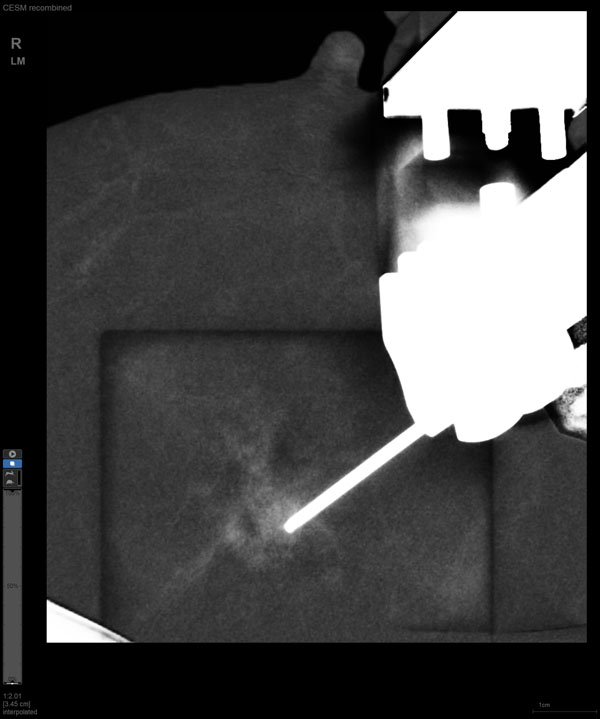

某患者增强磁共振成像MRI显示肿瘤周边有活性,中心区域有组织坏死。为得到准确的病理结果,穿刺靶区需避开肿物坏死区域。在与患者主管医生充分讨论后,放射科医生为患者行CEM引导下穿刺活检术。术中,CEM检查肿物同样显示为环形强化,巧妙避开坏死区域后,穿刺靶区选择了肿物增强早期明显强化区域,术程顺利,仅用时15分钟。术后该患者病理结果为浸润性导管癌Ⅱ级。

国内首台具有数字乳腺断层摄影(DBT)和CEM引导下穿刺功能的X线机